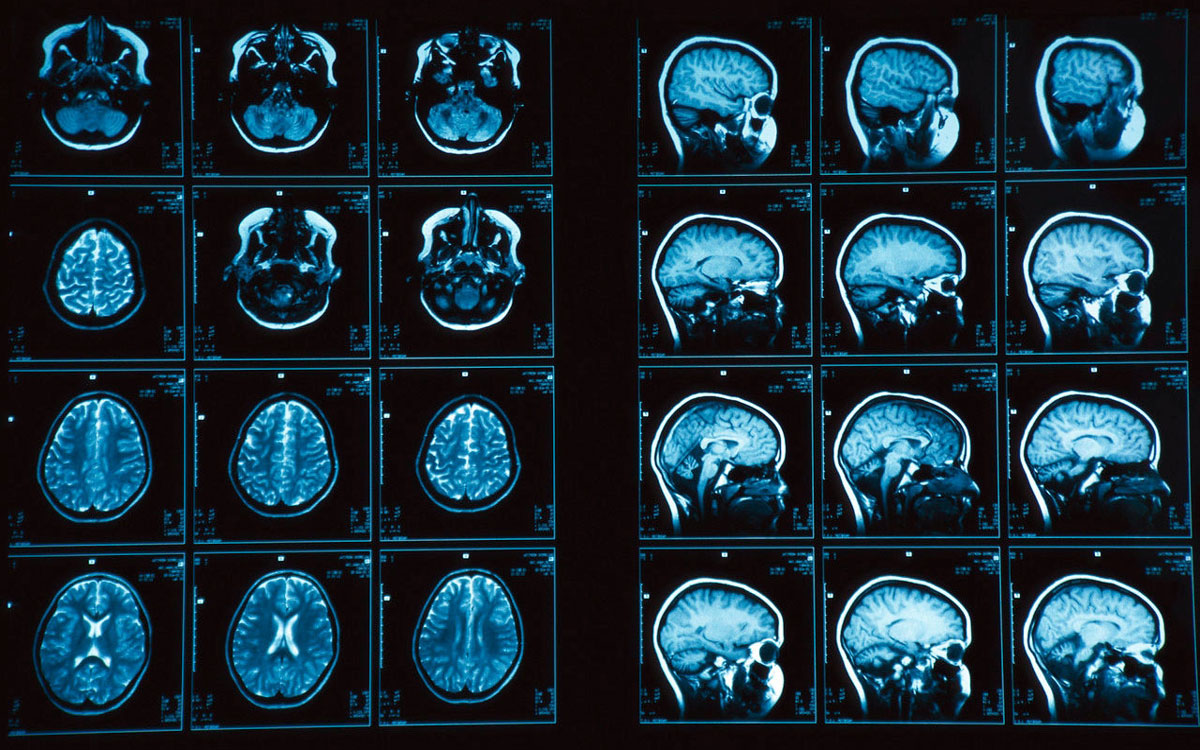

Різноплановість інформації, одержуваної при проведенні МРТ голови, обумовлена тим, що при цій діагностиці відбувається високоточне сканування відразу двох десятків шарів головного мозку. Сигнали томографа обробляються і трансформуються в тривимірне зображення.

Цей апарат являє собою об’ємну трубу, оточену магнітними елементами. Спеціальні датчики, які розташовуються біля голови, стануть постачальниками основної інформації. Сприйняті ними дані тут же з’являються на моніторі.